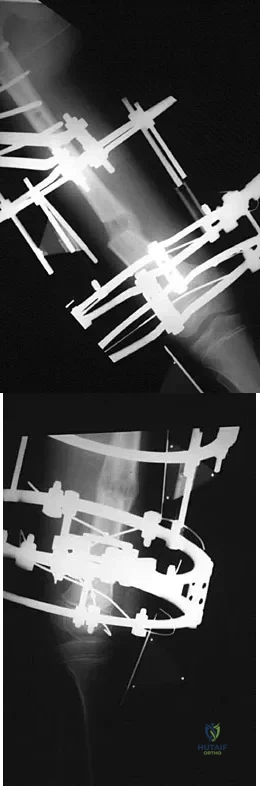

A teenager is undergoing a correction of deformity and lengthening of the femur. Distractions are proceeding as expected; however, during his 6-week follow-up examination, the patient reports that the distraction motors have become harder to turn over for the past 2 to 3 days. Figures 37a and 37b show current radiographs. What is the most likely complication being encountered?